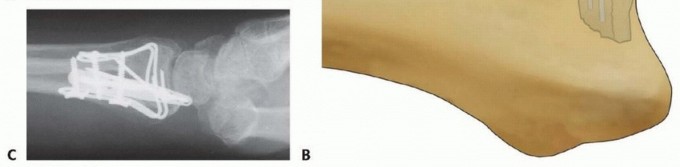

TECH FIG 8 • Radial column fixation with radial pin plate. A. Insertion of trans-styloid Kirschner wire. B,C. Creation of pin hook. D,E. Completion and impaction of pin hook. F,G. Completed radial column fixation. Select a distal pin hole and slide a radial pin plate over the trans-styloid Kirschner wire. Proximally, guide the plate under the tendons of the first dorsal compartment and secure it initially with a single 2.3-mm bone screw. Insert a second trans-styloid Kirschner wire through a nonadjacent distal pin hole. Use the previous technique to limit penetration of the Kirschner wire through the far cortex to 1 to 2 mm. Mark a reference point where the Kirschner wire crosses the surface of the plate. Withdraw the Kirschner wire 1 cm and cut it 1 cm or more above the reference mark ( TECH FIG 8B). Position the reference mark between the lower two posts of a wire bender and create a hook ( TECH FIG 8C). By starting the bend at the reference mark, this ensures that a Kirschner wire of proper length that extends 1 to 2 mm beyond the far cortex is created. Complete the bend with a pin clamp, overbending slightly to allow the hook to snap into an adjacent pin hole or over the edge of the plate ( TECH FIG 8D). With a free 0.045-inch Kirschner wire, predrill a hole to accept the end of the hook. Impact the Kirschner wire with a pin impactor and fully seat the hook ( TECH FIG 8E). Repeat the procedure with the second Kirschner wire. Complete proximal fixation with 2.3-mm cortical bone screws ( TECH FIG 8F,G). 2. ## Radial Column Fixation with Fixed-Angle Radial Column Plate 87 Expose and reduce the radial column with the technique described previously. Position the fixed-angle radial column plate and temporarily fix with a Kirschner wire both proximally and distally ( TECH FIG 9A). Confirm reduction of the radial column and plate position with the C-arm. Using fixed-angle drill guides, drill, measure, and insert locking fixation pegs of appropriate length into the distal fixed-angle holes in the plate and standard bone screws proximally into the shaft ( TECH FIG 9B-E).

TECH FIG 9 • Radial column fixation with fixed-angle radial column plate. A. Provisional placement of fixed-angle radial column plate. B. Drilling holes for distal fixed-angled pegs. C. Completed fixation. D. Unstable fracture injury films with segmental radial column comminution. E. Films 2 months postoperatively. Fixed-angle radial column support is used to avoid radial column shortening. 88 ## Ulnar Corner and Dorsal Wall Fixation Ulnar Pin Plate Through a dorsal approach, expose and reduce the dorsal ulnar corner fragment, dorsal wall fragment, or both. Insert a 0.045-inch Kirschner wire through the fragment ( TECH FIG 10A), angled proximally and slightly radially to purchase the far cortex of the proximal fragment. Insert structural bone graft into the metaphyseal defect if present to support the subarticular surface. If the plate is aligned along the pulnar border of the shaft, add a 15-degree torsional bend to the plate (twist the proximal end of the plate into slight supination). Often, a little extra extension can be contoured at the distal end of the plate ( TECH FIG 10B).

TECH FIG 10 • Ulnar corner fixation with an ulnar pin plate. A. Insertion of the interfragmentary Kirschner wire. B. Contouring the plate. C. Application of the plate and insertion of the initial fixation screw. D. Fixation completed. E,F. Radial and ulnar pin plate fixation of a three-part articular pattern (radial column and ulnar corner fragment). Slide the plate over the Kirschner wire and fix it proximally with a 2.3-mm bone screw ( TECH FIG 10C). Insert a second Kirschner wire if the fragment is large enough. Create and impact hooks as described for the radial pin plate ( TECH FIG 10D-F). If the Kirschner wire tips protrude beyond the volar cortex, they can be cut flush to the bone surface through a volar incision. Dorsal Buttress Pin Through a dorsal approach, expose and reduce the dorsal ulnar corner fragment, dorsal wall fragment, or both. Insert structural bone graft into the metaphyseal defect if present to support the subarticular surface. Insert two 0.045-inch Kirschner wires through the dorsal cortex and behind the subchondral bone; check the position with 89 the C-arm ( TECH FIG 11A). The Kirschner wires should be separated by about 1 cm and should be transverse to the longitudinal axis of the shaft; on the lateral view, it may be necessary to angle the Kirschner wires proximally to avoid penetration into the joint if the entry site is near the dorsal rim. Initially placing a dorsal buttress pin upside-down on the bone can be helpful as a template in order to visualize the proper position and insertion angle of the Kirschner wires ( TECH FIG 11B). Particular attention should be given to determining whether the insertion angle should include some pronation or supination in order to avoid torsion of the wire form as it is secured proximally.

TECH FIG 11 • Dorsal buttress pin fixation. A. The position of the Kirschner wires is checked with a Carm before inserting the implant. B. Placing an implant upside-down on bone to template the trajectory of the Kirschner wires. C. Inserting the dorsal buttress pin. D. Buttress pin fixation completed. E,F. Fixation of a three-part articular fracture with radial column and ulnar corner fragment with radial column plate and dorsal buttress pin. Ensure that the leading tips of the legs of the dorsal buttress pin are straight and cut to the required length. Leave the ulnar leg 2 to 3 mm longer than the radial leg so one leg can be engaged at a time. Direct the legs proximally if needed to match the insertion angle of the Kirschner wires. Place the ulnar leg of the buttress pin adjacent to the insertion site of the ulnar Kirschner wire, and then withdraw the Kirschner wire and immediately engage the leg in the hole ( TECH FIG 11C). Repeat with the radial Kirschner wire to engage the radial leg of the buttress pin. Impact and seat the buttress pin ( TECH FIG 11D). Fine-tune the reduction and complete the fixation proximally with one or two 2.3-mm cortical bone screws and washers ( TECH FIG 11E,F). If needed, a blocking screw can be placed just proximal to the end of the buttress pin to prevent shortening of the fragment. Dorsal Hook Plate Fixation Dorsal hook plates are another alternative for fixation of dorsal fragments. Expose and reduce ulnar corner and/or dorsal wall fragments according to the technique described previously. Position and insert a 0.045-inch Kirschner guidewire distally along the intended path of the hooks of the plate. Confirm the position with the C-arm. If needed, predrill the holes for insertion of the hooks. In osteoporotic bone, the hooks can be simply pushed into the fragment ( TECH FIG 12A). Verify the position and reduction with C-arm and complete fixation with proximal bone screws ( TECH FIG 12B). 90